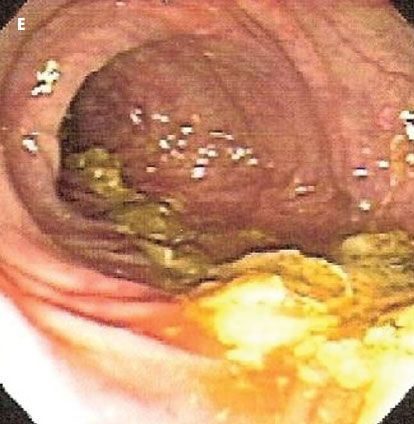

At our advice, the patient-who was taking 16 medications in total-discontinued aspirin therapy. Thereafter, the patient’s health improved and a diagnosis of NSAID-induced colitis was made. CT (D) and colonoscopy (E) done 6 months later showed complete resolution of the lesion. Our patient is currently controlling her arthritic joint pain with acetaminophen.